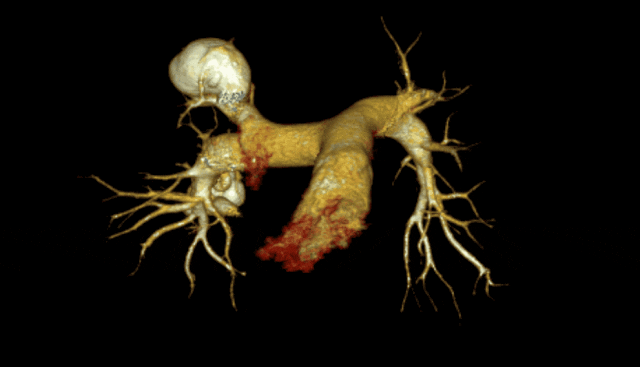

CT提示:盆腔静脉扩张,左卵巢静脉扩张。

超选左肾静脉,左侧卵巢静脉,造影见卵巢静脉曲张明显,直径13 mm,盆腔大量曲张静脉显影。